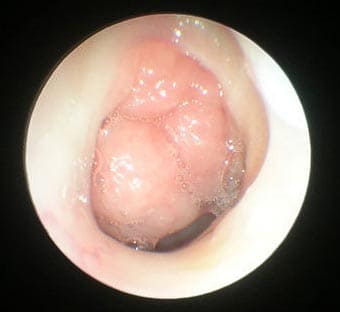

Аденоиды 3 степени, фото через эндоскоп

Клиническая картина (выраженность патологических изменений) не всегда соответствует степени увеличения аденоидов. Бывает так, что аденоиды первой и второй степени могут вызывать сильное затруднение носового дыхания, резкое снижение слуха, а аденоиды третей степени не вызывают видимых нарушений. Поэтому только по размеру однозначно нельзя сказать, что нужно делать – лечить консервативно или радикально (удалять аденоиды).